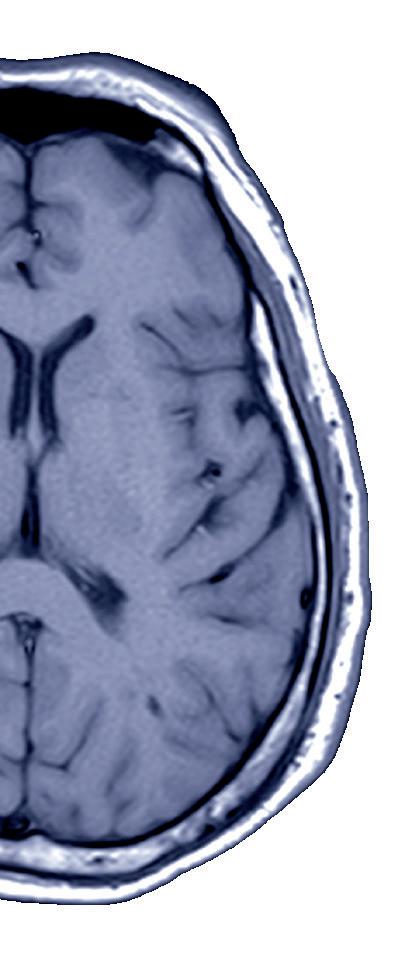

Ten years of MR CLEAN: Stroke thrombectomy’s evolution and ongoing challenges

Charles Majoie Diederik Dippel

This year, 25 October marks a full decade since the initial presentation of results from the MR CLEAN randomised controlled trial (RCT), which—along with multiple other RCTs—instigated the rapid expansion of mechanical thrombectomy in the treatment of acute ischaemic stroke. Here, two of MR CLEAN’s leading clinical investigators, Charles Majoie (Amsterdam, The Netherlands) and Diederik Dippel (Rotterdam, The Netherlands), reflect on the impact of the study and outline remaining areas for improvement regarding thrombectomy treatments.

Within a decade, the landscape of acute stroke treatment has changed drastically. Looking back now, to when it all began at the 9th World Stroke Congress (WSC; 22–25 October 2014, Istanbul, Türkiye), shows that much has been done and changed, and many patients have benefitted—but we are not finished yet!

Here, we present a historical summary and also a global overview of the availability of this highly effective treatment for ischaemic stroke.

Evolution of EVT

Before 2014, thrombectomy—or endovascular therapy (EVT)—was performed in selected cases, mostly under research protocols or in major stroke centres. The MR CLEAN trial helped to change that by providing high-quality evidence, prompting rapid adoption in clinical practice. By 2015, after MR CLEAN and subsequent trials, EVT became part of routine stroke care guidelines, resulting in significant global growth.

The pivotal MR CLEAN trial was first presented at WSC on 25 October 2014, marking a turning point in the treatment of ischaemic stroke. This groundbreaking study highlighted the benefits of EVT for large vessel occlusion (LVO) strokes, and it paved the way for global changes in stroke management.

MR CLEAN was published in the New England Journal of Medicine in January 20151, followed by publication of six other landmark trials: ESCAPE, EXTEND-IA, SWIFT PRIME, REVASCAT, THRACE and PISTE, and an individual patient data metaanalysis.2 These trials confirmed the efficacy of EVT in treating acute ischaemic stroke, solidifying its place

as the standard of care. The profound impact of these studies is evidenced by widespread citations and recognition in stroke literature.

Over the past decade, the indications for EVT have expanded significantly. Initially limited to LVO within 0–6 hours of stroke onset, it now encompasses treatment windows extended to 24 hours, and patients with small to large infarcts.3 Treatment is no longer confined by age or certain preexisting conditions, making EVT a viable option for a broader range of stroke patients.

The expanded eligibility criteria for EVT—including patients presenting up to 24 hours after stroke onset and those with more extensive infarcts—has dramatically increased the number of potential candidates for the procedure. This has also contributed to the surge in thrombectomy numbers worldwide.

In recent years, China and India have made efforts to scale up thrombectomy services, given their large populations and increasing burden of stroke. This can be seen with the increased number of thrombectomies in China, rising from 20,000 in 2019 to 72,000 in 2023. But, although growth has been rapid, these countries are still catching up in terms of the ratio of thrombectomy procedures relative to stroke incidence. In 2023, in India, only 4,500 out of 375,000 patients who qualified for stroke intervention received this lifesaving treatment.

Further challenges

In 2016, roughly 30,000–40,000 thrombectomies were performed across the globe. By 2020, this number grew substantially to more than 100,000 annual procedures, driven by better access, expanded treatment windows, and the broadening criteria for patient eligibility. For 2022–2023, estimates suggest over 150,000 EVT procedures globally per year, with regions like North America and Europe accounting for a large proportion of these numbers.4

However, despite this remarkable growth, the lack of adequate facilities and trained professionals in many regions continues to hinder global

The success of acute thrombectomy has highlighted the need for adequate post-intervention stroke unit care and basic rehabilitation, in order to make the effect of the treatment sustainable. Stroke unit care benefits more patients, and its overall health impact—on a population level— is at least as significant as the effect of thrombectomy.

The increasing demand for thrombectomies has also placed a significant burden on interventional teams, leading to an increased risk of burnout. The intensive nature of EVT